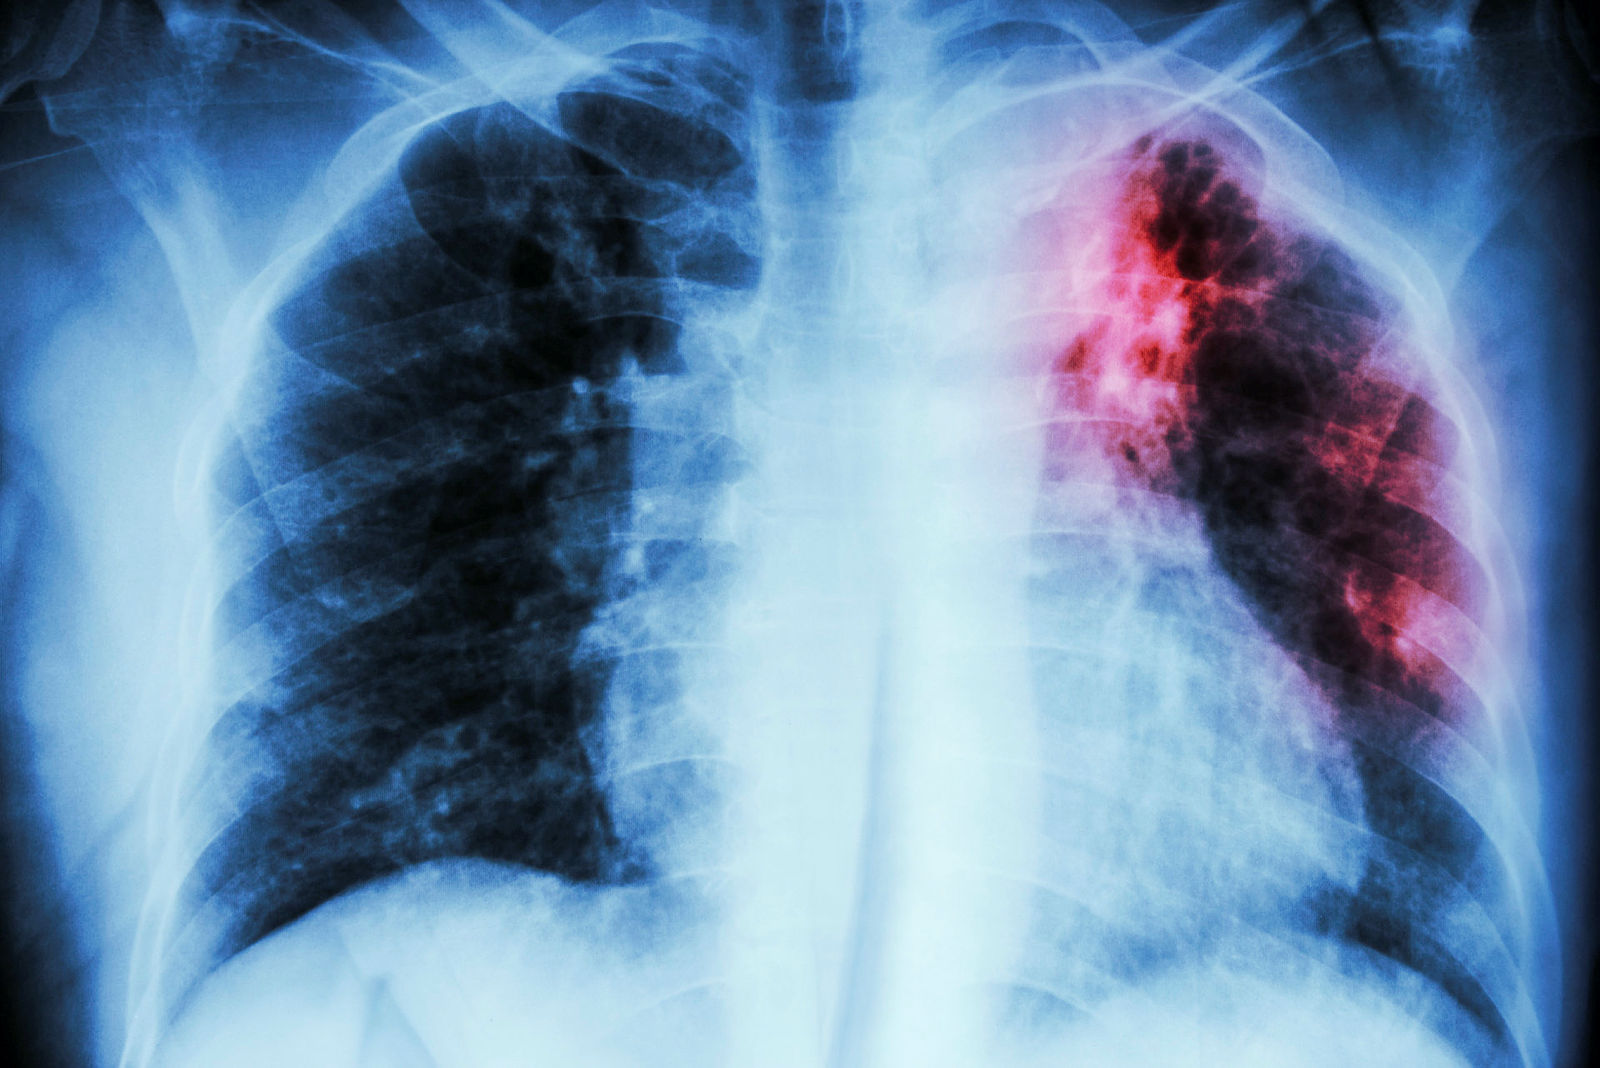

Antallet tilfeller tuberkulose i Norge økte i 2022

Antallet meldte tilfeller med tuberkulosesykdom økte fra 155 tilfeller i 2021 til 174 i 2022.

De to siste årene har det vært en økning i antall tilfeller av multiresistent tuberkulose (MDR TB), som nå utgjør over 7 prosent av det totale antallet tuberkulosetilfeller i Norge. Andelen øker også på verdensbasis.

– Denne formen for tuberkulose er vanskeligere og mer krevende å behandle. Det er et stort etterslep i tuberkulosediagnostikk og -behandling i en rekke land som følge av pandemien, og vi ser en økende dødelighet av sykdommen globalt. Dette gir grunn til bekymring for utviklingen framover, sier overlege Karine Nordstrand i en pressemelding.